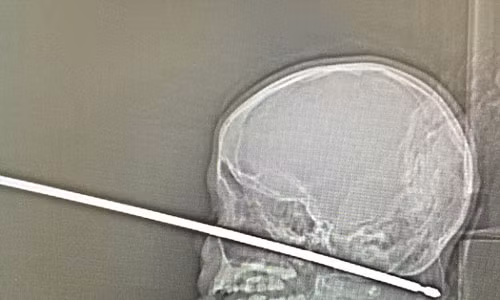

| Cái xiên xuyên qua má trái của cậu bé và xuyên vào sọ. |